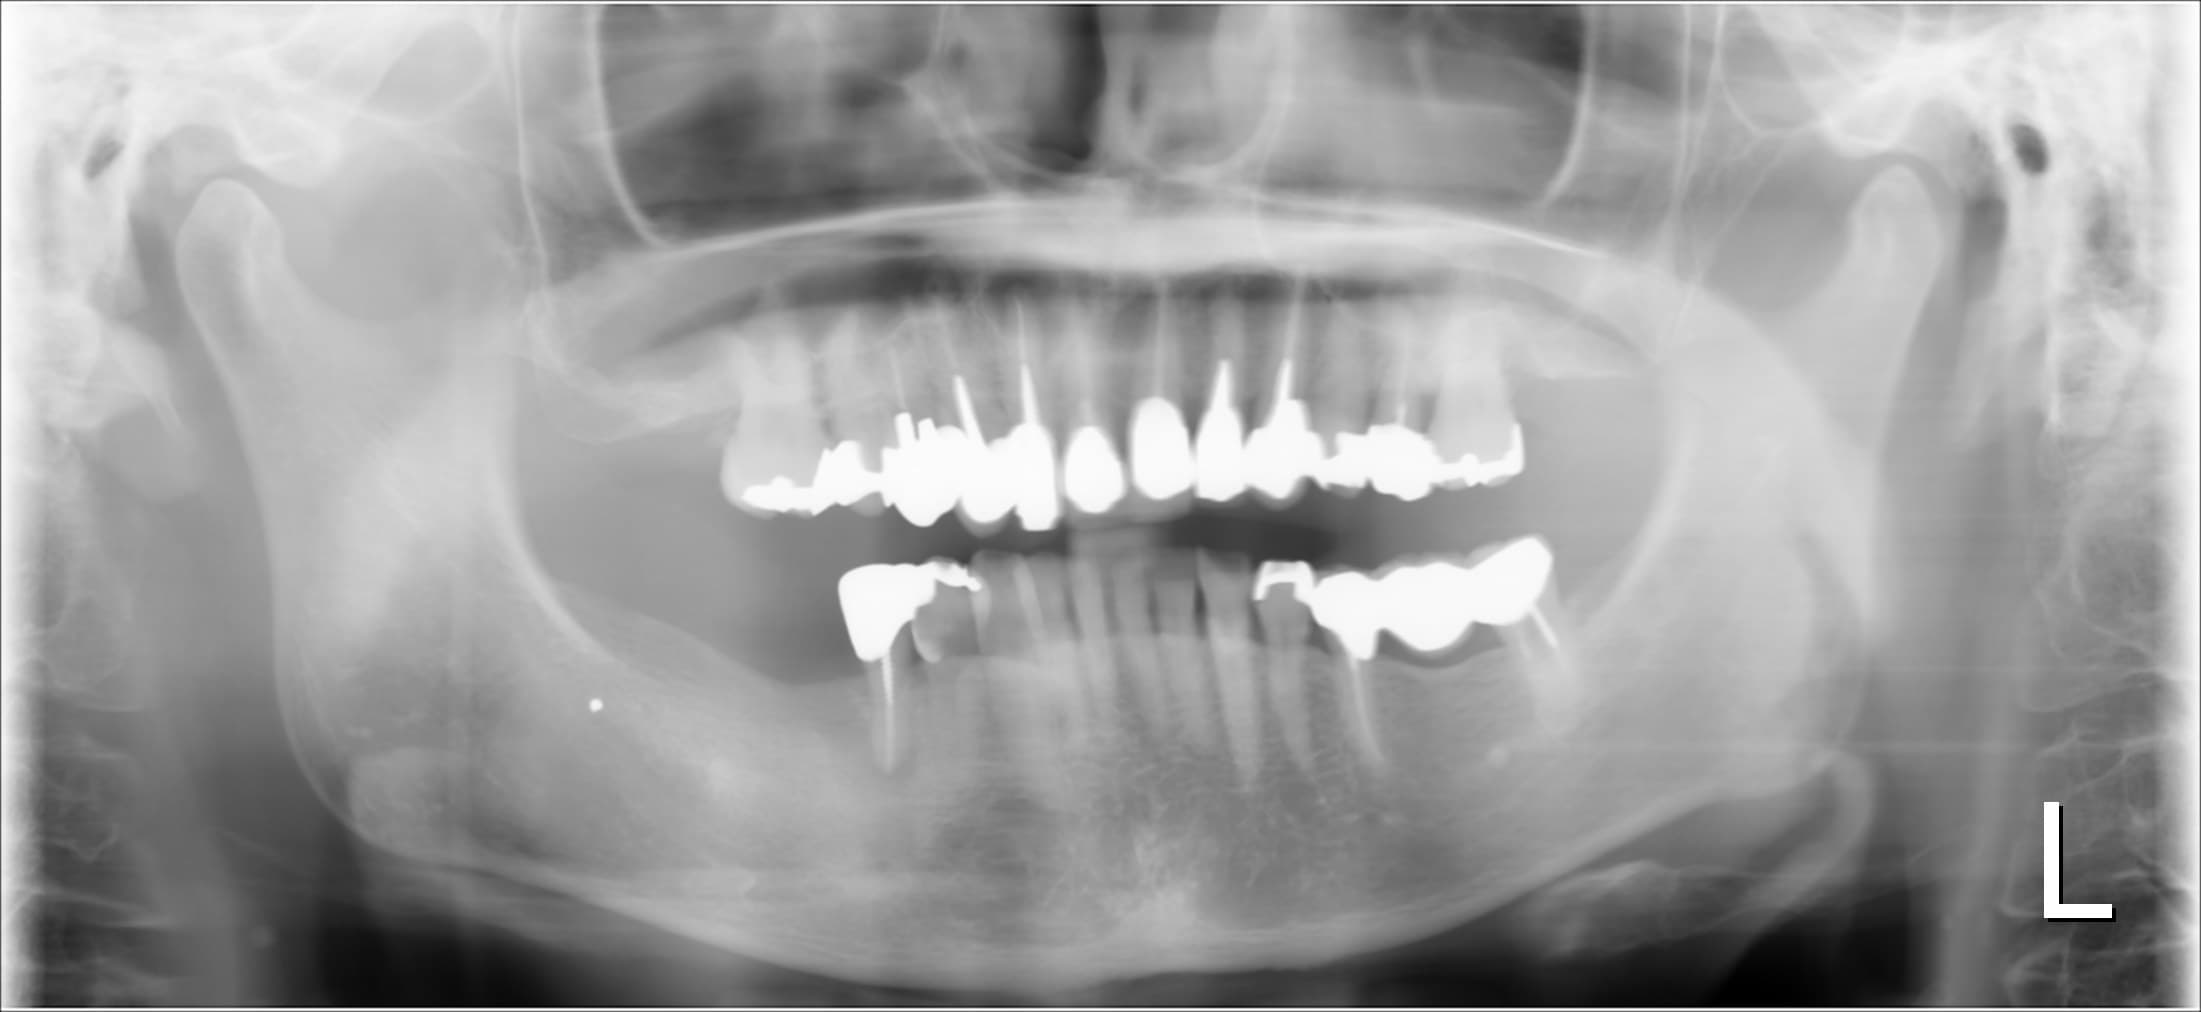

従来は、下の様な平面上(2次元)のレントゲン写真が主流でした。

<パノラマ写真>

左上(写真では右上)の奥を拡大したレントゲン写真

一部とても深いポケットがあり、歯を支える骨が大きく溶けています。従来のレントゲンでは分かりにくいですよね。